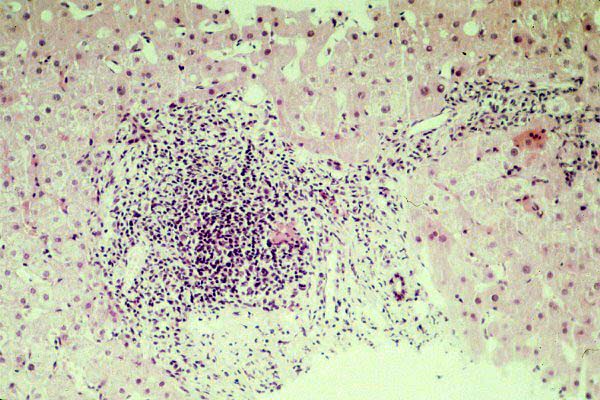

fig. 2

Figura 2.- Espacio porta con infiltrado inflamatorio polimorfo dispuesto en torno a un ducto biliar interlobular. Obsérvese la presencia de un granuloma epitelioide.